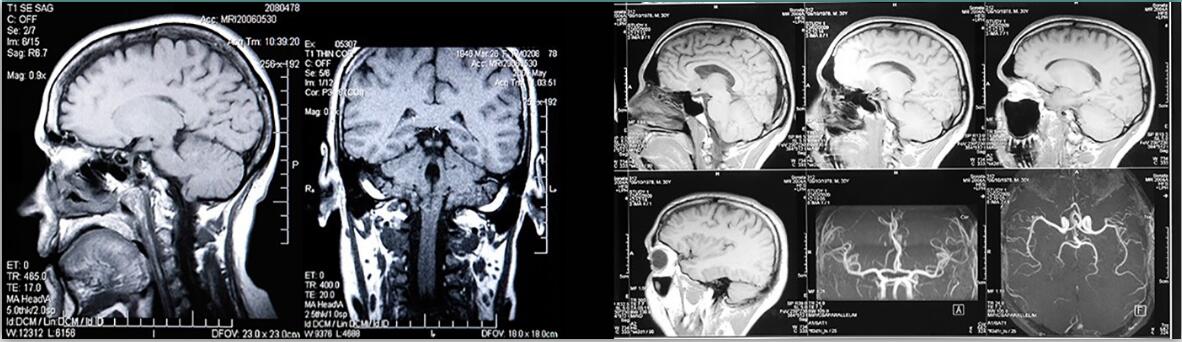

颅内血管流动模型,亚克力

颅内血管流动模型

该流动模型旨在真实准确地模拟颅内脉管系统的真实血管直径、血管长度和复杂几何形状,在基底分叉处具有可选的经典浆果球动脉瘤,直径可达 12.5 毫米。

与我们的 CompuFlow 1000 或 CompuFlow 1000 MR 一起使用时测试成像技术几何保真度的里想模型